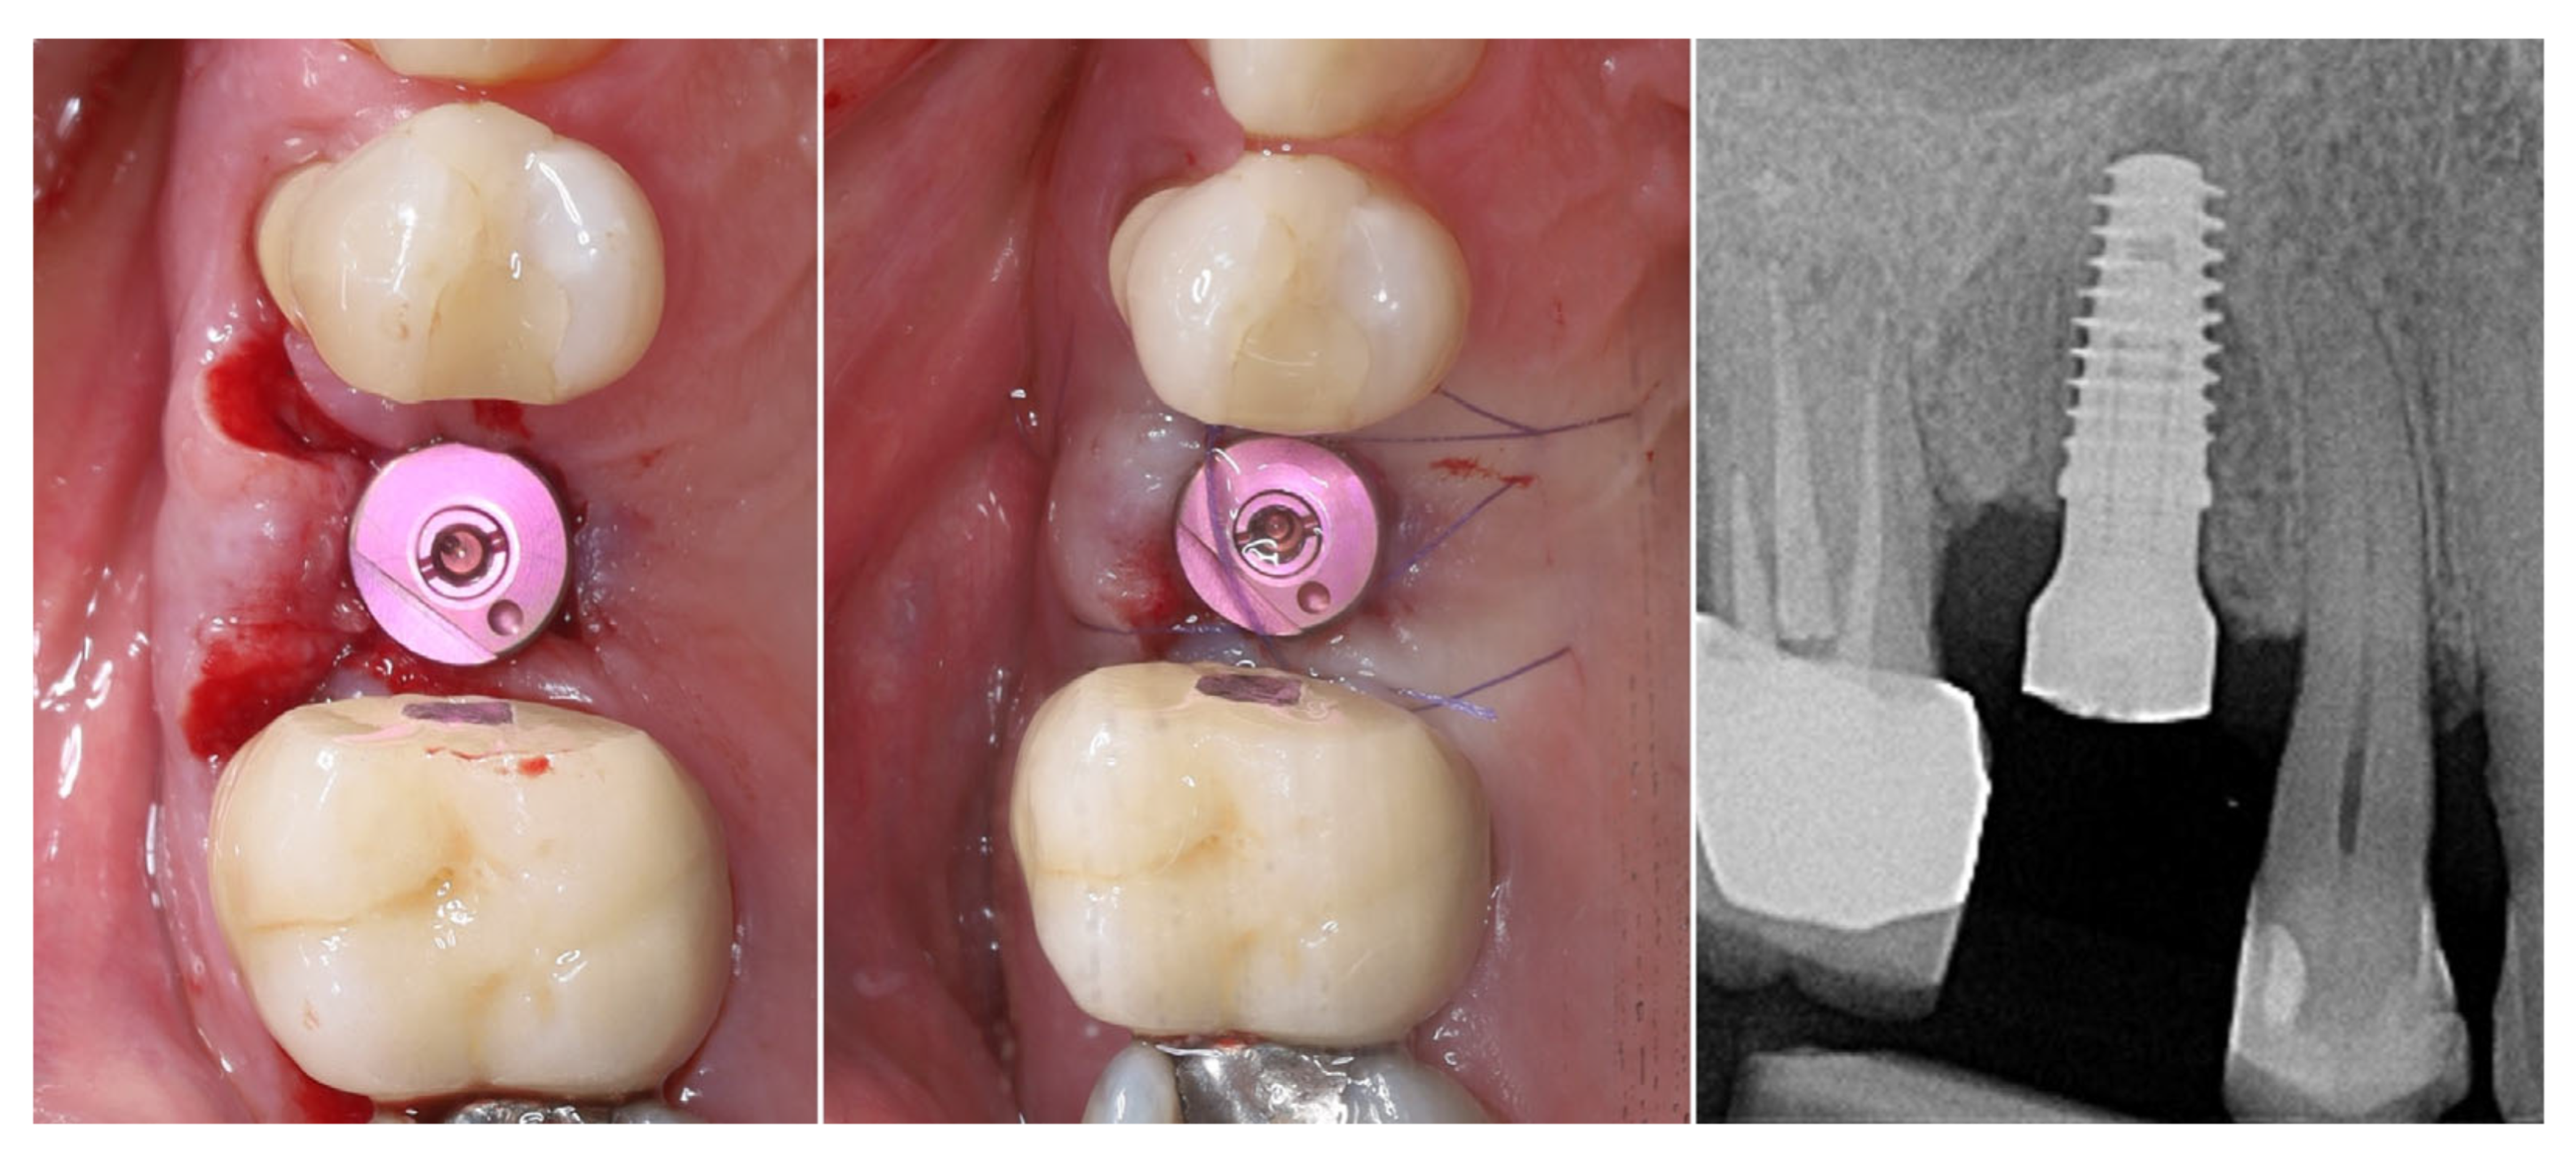

2. Materials and Methods—Clinical Case